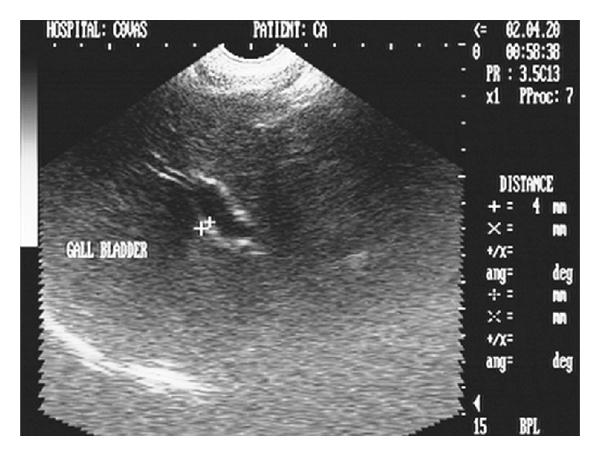

Hepatic disease is often treatable and has a predictable prognosis when a definitive diagnosis is made. The aim of clinicopathological evaluation of hepatobiliary affections is to identify and characterize hepatic damage and dysfunction, identify possible primary causes of secondary liver disease, differentiate causes of icterus, evaluate potential anaesthetic risks, assess prognosis and response to xenobiotics, and monitor response to therapy. This paper describes the different diagnostic methods and imaging techniques employed in diagnosis of hepatobiliary affections in dogs. Besides reviewing the significant clinical manifestations and imaging structural abnormalities in diagnostic approach to different hepatic affections, it also depicts radiographic, ultrasonographic, and wherever applicable, the laparoscopic characterization of different hepatic affections and target lesions encountered in clinical cases presented in the Teaching Veterinary Clinical Complex, COVAS, Palampur in the year 2007-2008.

肝病通常是可治疗的,一旦做出明确诊断,其预后是可预测的。肝胆疾病临床病理评估的目的是识别和描述肝损伤及功能障碍,确定继发性肝病可能的主要病因,鉴别黄疸的病因,评估潜在的麻醉风险,评估预后及对外源化学物质的反应,并监测治疗反应。本文描述了用于诊断犬肝胆疾病的不同诊断方法和成像技术。除了回顾不同肝病诊断方法中的重要临床表现和成像结构异常外,还描述了2007 - 2008年在帕兰普尔兽医临床综合教学中心(COVAS)出现的临床病例中不同肝病及目标病变的放射学、超声学特征,以及在适用情况下的腹腔镜特征。